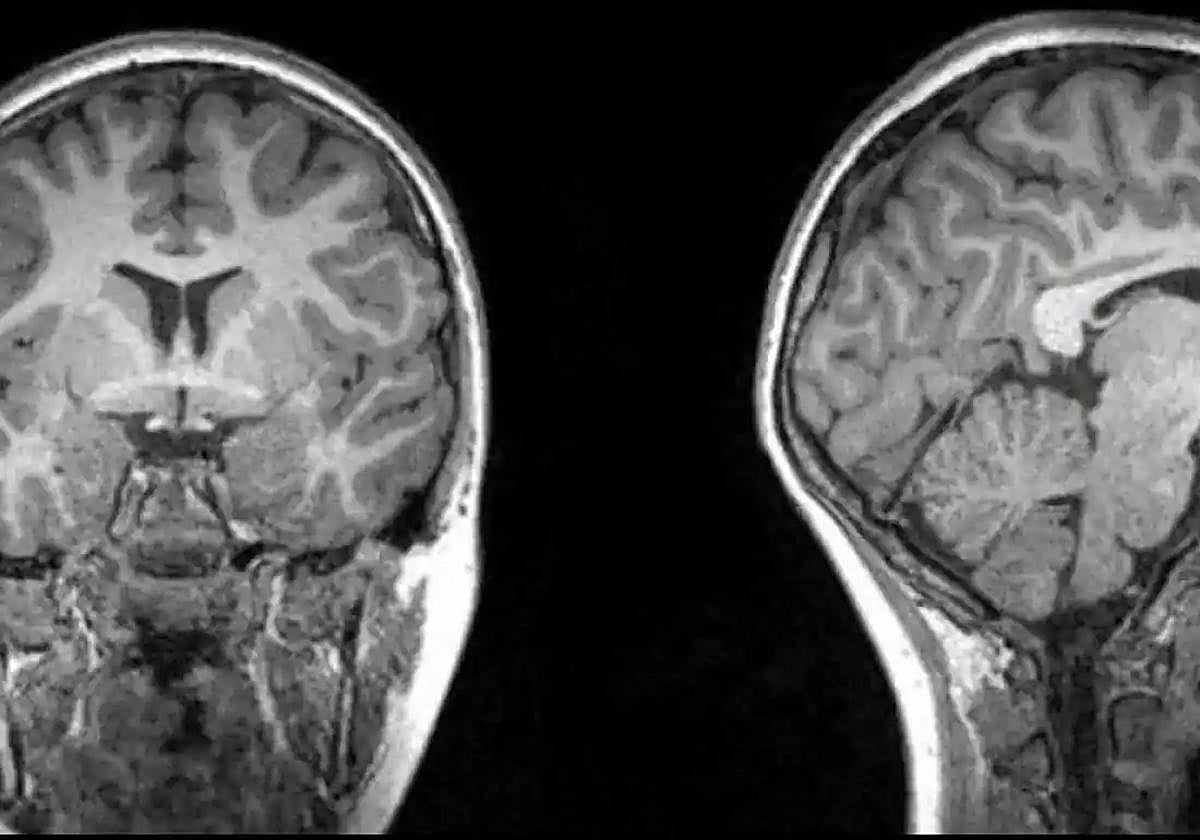

En este sentido, y de acuerdo con diversos estudios, el uso de algunos fármacos a largo plazo puede aumentar el riesgo de ciertas enfermedades. Es el caso de enfermedades mentales degenerativas como la demencia, el alzhéimer y el párkinson. Consideradas las tres, como uno de los principales retos en términos de la salud neurológica de la población mundial. En concreto, un estudio reciente elaborado por investigadores de la Universidad de Harvard, ha desvelado que el consumo de fármacos tan populares como ansiolíticos, podrían dañar el cerebro.

En España, y según datos de la Sociedad Española de Neurología, se estima que el Alzhéimer afecta entre 500.000 y 800.000 personas. Mientras tanto, el Parkinson puede llegar a tener una prevalencia entre 120.000 y 300.000 personas. Si bien se trata de enfermedades neurodegenerativas, cuyos factores de riesgo aumentan con la edad y otras enfermedades. El estudio de la Universidad de Harvard, señala que el uso de ansiolíticos está fuertemente relacionado con el riesgo de sufrir demencia, Alzhéimer o Parkinson. Este fármaco, usado principalmente para tratar trastornos de ansiedad y sueño, actúa directamente sobre el sistema nervioso central produciendo un efecto calmante.